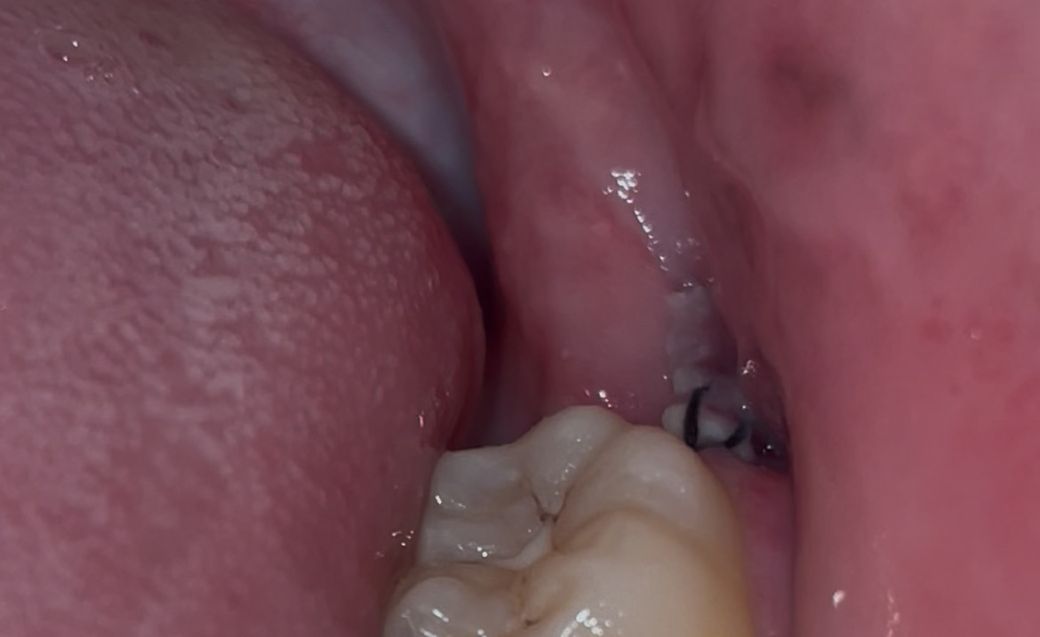

매복사랑니 발치 실밥 밑에 음식물이 끼었는데 안빠져요

실밥 밑에 꼈는데 가글 열심히 해도 안빠집니다ㅜㅜ 주사기 사용해서 물 뿌렸는데도 빠지지 않아요. 오늘 내일 치과도 안여는데 어떻게 해야하나요? 치간칫솔로 건들면 안되겠죠?

• 1번 째 사진

잇몸이 아물면서 생기는 자연스러운 현상입니다. 이물질이 아니니 너무 걱정하지 않으셔도 됩니다.

실밥 밑에 꼈는데 가글 열심히 해도 안빠집니다ㅜㅜ 주사기 사용해서 물 뿌렸는데도 빠지지 않아요. 오늘 내일 치과도 안여는데 어떻게 해야하나요? 치간칫솔로 건들면 안되겠죠? -> 치간칫솔은 자극되니 하지마시고, 그냥 뒀다가 평일에 치과가세요